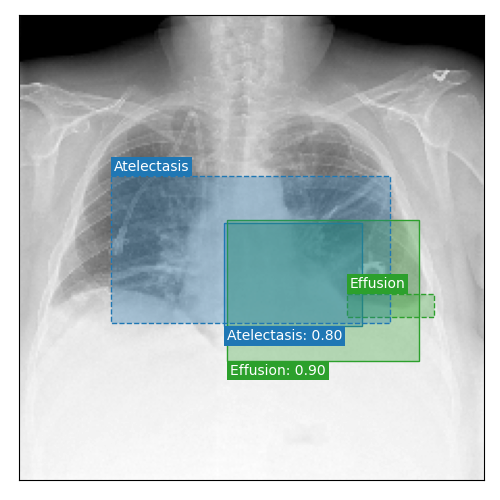

Qualitative Results

As shown in Fig. 4 Loc-ADPD detects cardiomegaly almost perfectly, as it is always exactly localized at one anatomical region. Other pathologies are detected but often with too large or too small boxes as they only cover parts of anatomical regions or stretch over several of them, which cannot be completely corrected using WBF. Detection also works well for predicting several overlapping pathologies. For qualitative comparisons between Loc-ADPD and MIL-ADPD, we refer to Appendix 0.B.